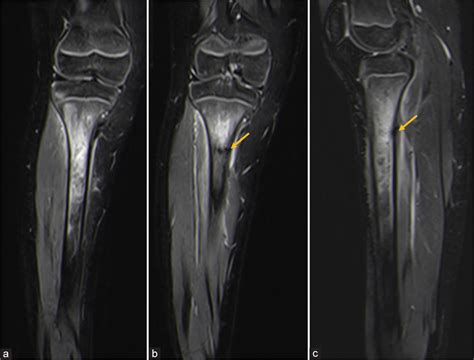

Doctors may suggest more sensitive imaging techniques if clinical symptoms remain high despite a clear X-ray. An MRI is often considered the "gold standard" for diagnosing a stress fracture tibia because it can detect bone marrow edema (swelling inside the bone), which is an early sign of stress-related injury before a fracture line even forms.